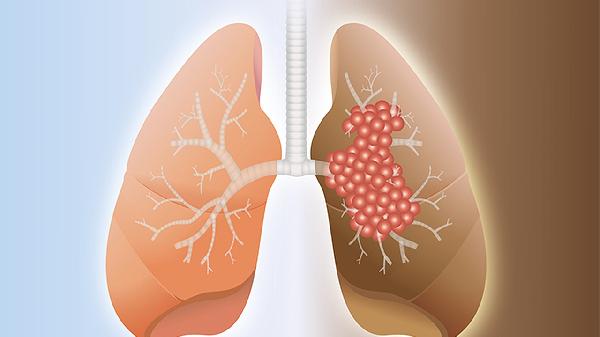

CT检查不能完全确诊肺癌,但可作为重要筛查手段。肺癌确诊需结合病理活检、支气管镜等检查综合判断。CT主要用于发现肺部异常病灶并评估其形态特征。

建议发现肺部异常阴影时,应在呼吸科或胸外科医生指导下完善肿瘤标志物检测、PET-CT等功能影像检查。对于高度可疑病灶,需通过经皮肺穿刺活检、支气管镜活检或手术切除获取组织标本,病理检查发现癌细胞才是确诊肺癌的金标准。40岁以上长期吸烟者建议每年进行低剂量CT筛查,同时避免过度依赖单一检查结果。